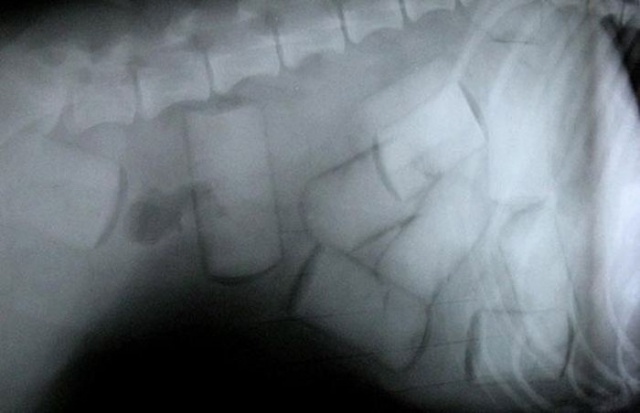

| Thậm chí bọn tội phạm còn giả vờ gãy chân để giấu hàng. |